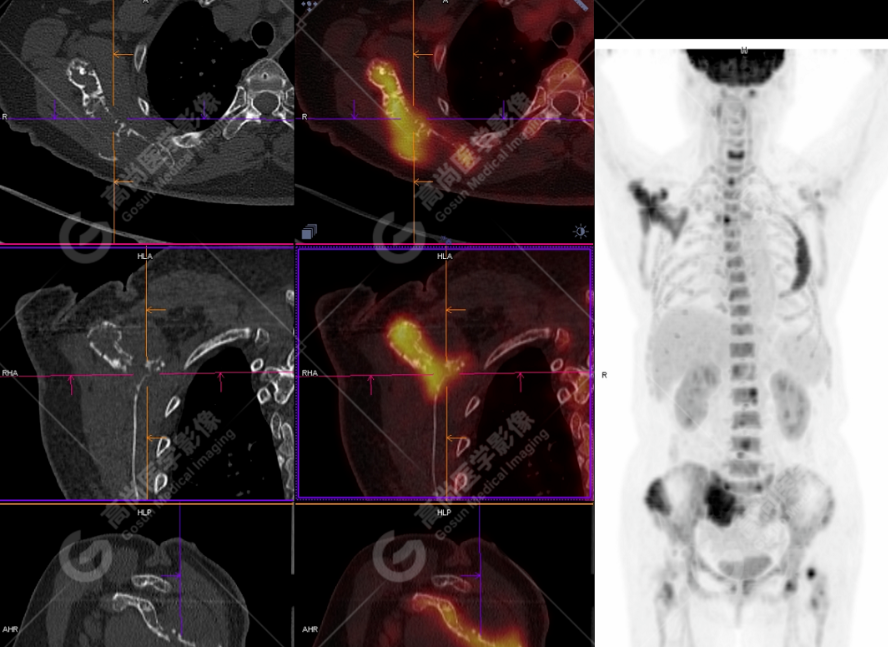

颅骨、寰椎前弓左侧份、第 6 颈椎、双侧肩胛骨(右侧为著)、左侧第 4 肋骨、第 1 胸椎、第 4 胸椎、第 2 腰椎及附件、第 4 腰椎及附件、骶骨、右侧髂骨、左侧坐骨结节、左侧股骨颈、双侧股骨小转子等均不同程度骨质吸收、破坏,其中右侧肩胛骨、左侧第 4 肋骨及骶骨右侧份软组织肿块影形成,上述病变均考虑恶性肿瘤(血液系统来源,多发骨髓瘤可能性大),建议右侧髂骨翼穿刺活检明确。

(4)PET-CT 影像表现:在溶骨性破坏区出现相重叠的 18F- FDG 高代谢区;通常呈弥漫性高代谢区。